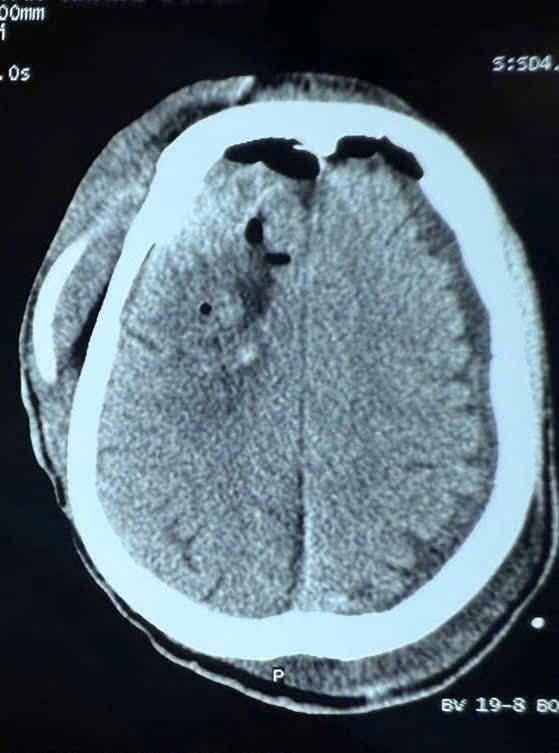

Khoa Ngoại thần kinh – Bệnh viện 19-8 vừa phẫu thuật thành công 1 trường hợp bệnh nhân nam 55 tuổi bị xuất huyết não trán – thái dương phải do ngã sau cơn động kinh.

Theo đó, bệnh nhân vào viện trong tình trạng lơ mơ, Glasgow 12 điểm, liệt nửa người trái.

Bệnh nhân đã được phẫu thuật cấp cứu lấy máu tụ kịp thời.

Sau mổ 2 ngày, bệnh nhân tỉnh, GCS (Glasgow Coma Scale) 15 điểm (có nghĩa là bệnh nhân hoàn toàn tỉnh táo), cai được thở máy, cơ lực nửa người trái cải thiện, phục hồi tốt.

Hình ảnh chấn thương não sau cơn động kinh - Ảnh BSCC